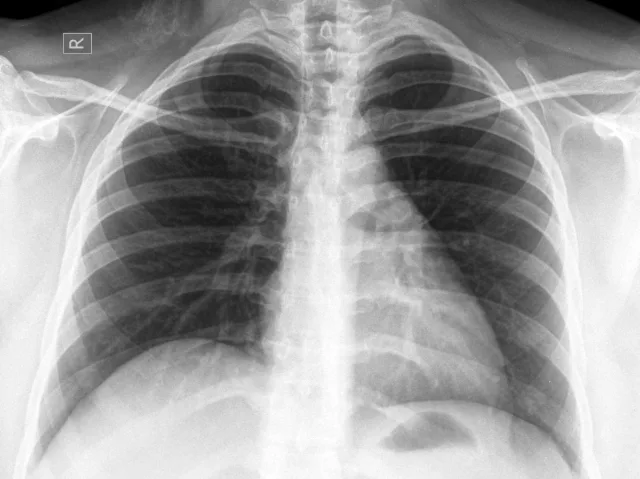

Chest Pain Evaluation in Frisco, Sherman & Carrollton, TX

Chest pain can be sudden, uncomfortable, and frightening — and it should never be ignored. At Pioneer Medical Associates, our chest pain evaluation clinic in Frisco, TX provides comprehensive, timely assessment and treatment for patients across Frisco, Sherman, Carrollton, and surrounding North Texas communities. Whether your chest pain is related to a cardiac condition, acid reflux, muscle strain, or anxiety, our board-certified physicians use advanced diagnostic testing to identify the cause quickly and create a personalized treatment plan to protect your long-term heart health.

Our experienced medical team takes every case of chest pain seriously. Using advanced diagnostic testing and evidence-based care, we work quickly to determine the underlying cause of your symptoms and develop a personalized treatment plan. Whether your chest pain is related to heart disease, acid reflux, muscle strain, anxiety, or another medical condition, our goal is to provide accurate diagnosis, prompt treatment, and peace of mind — while protecting your long-term cardiovascular health.